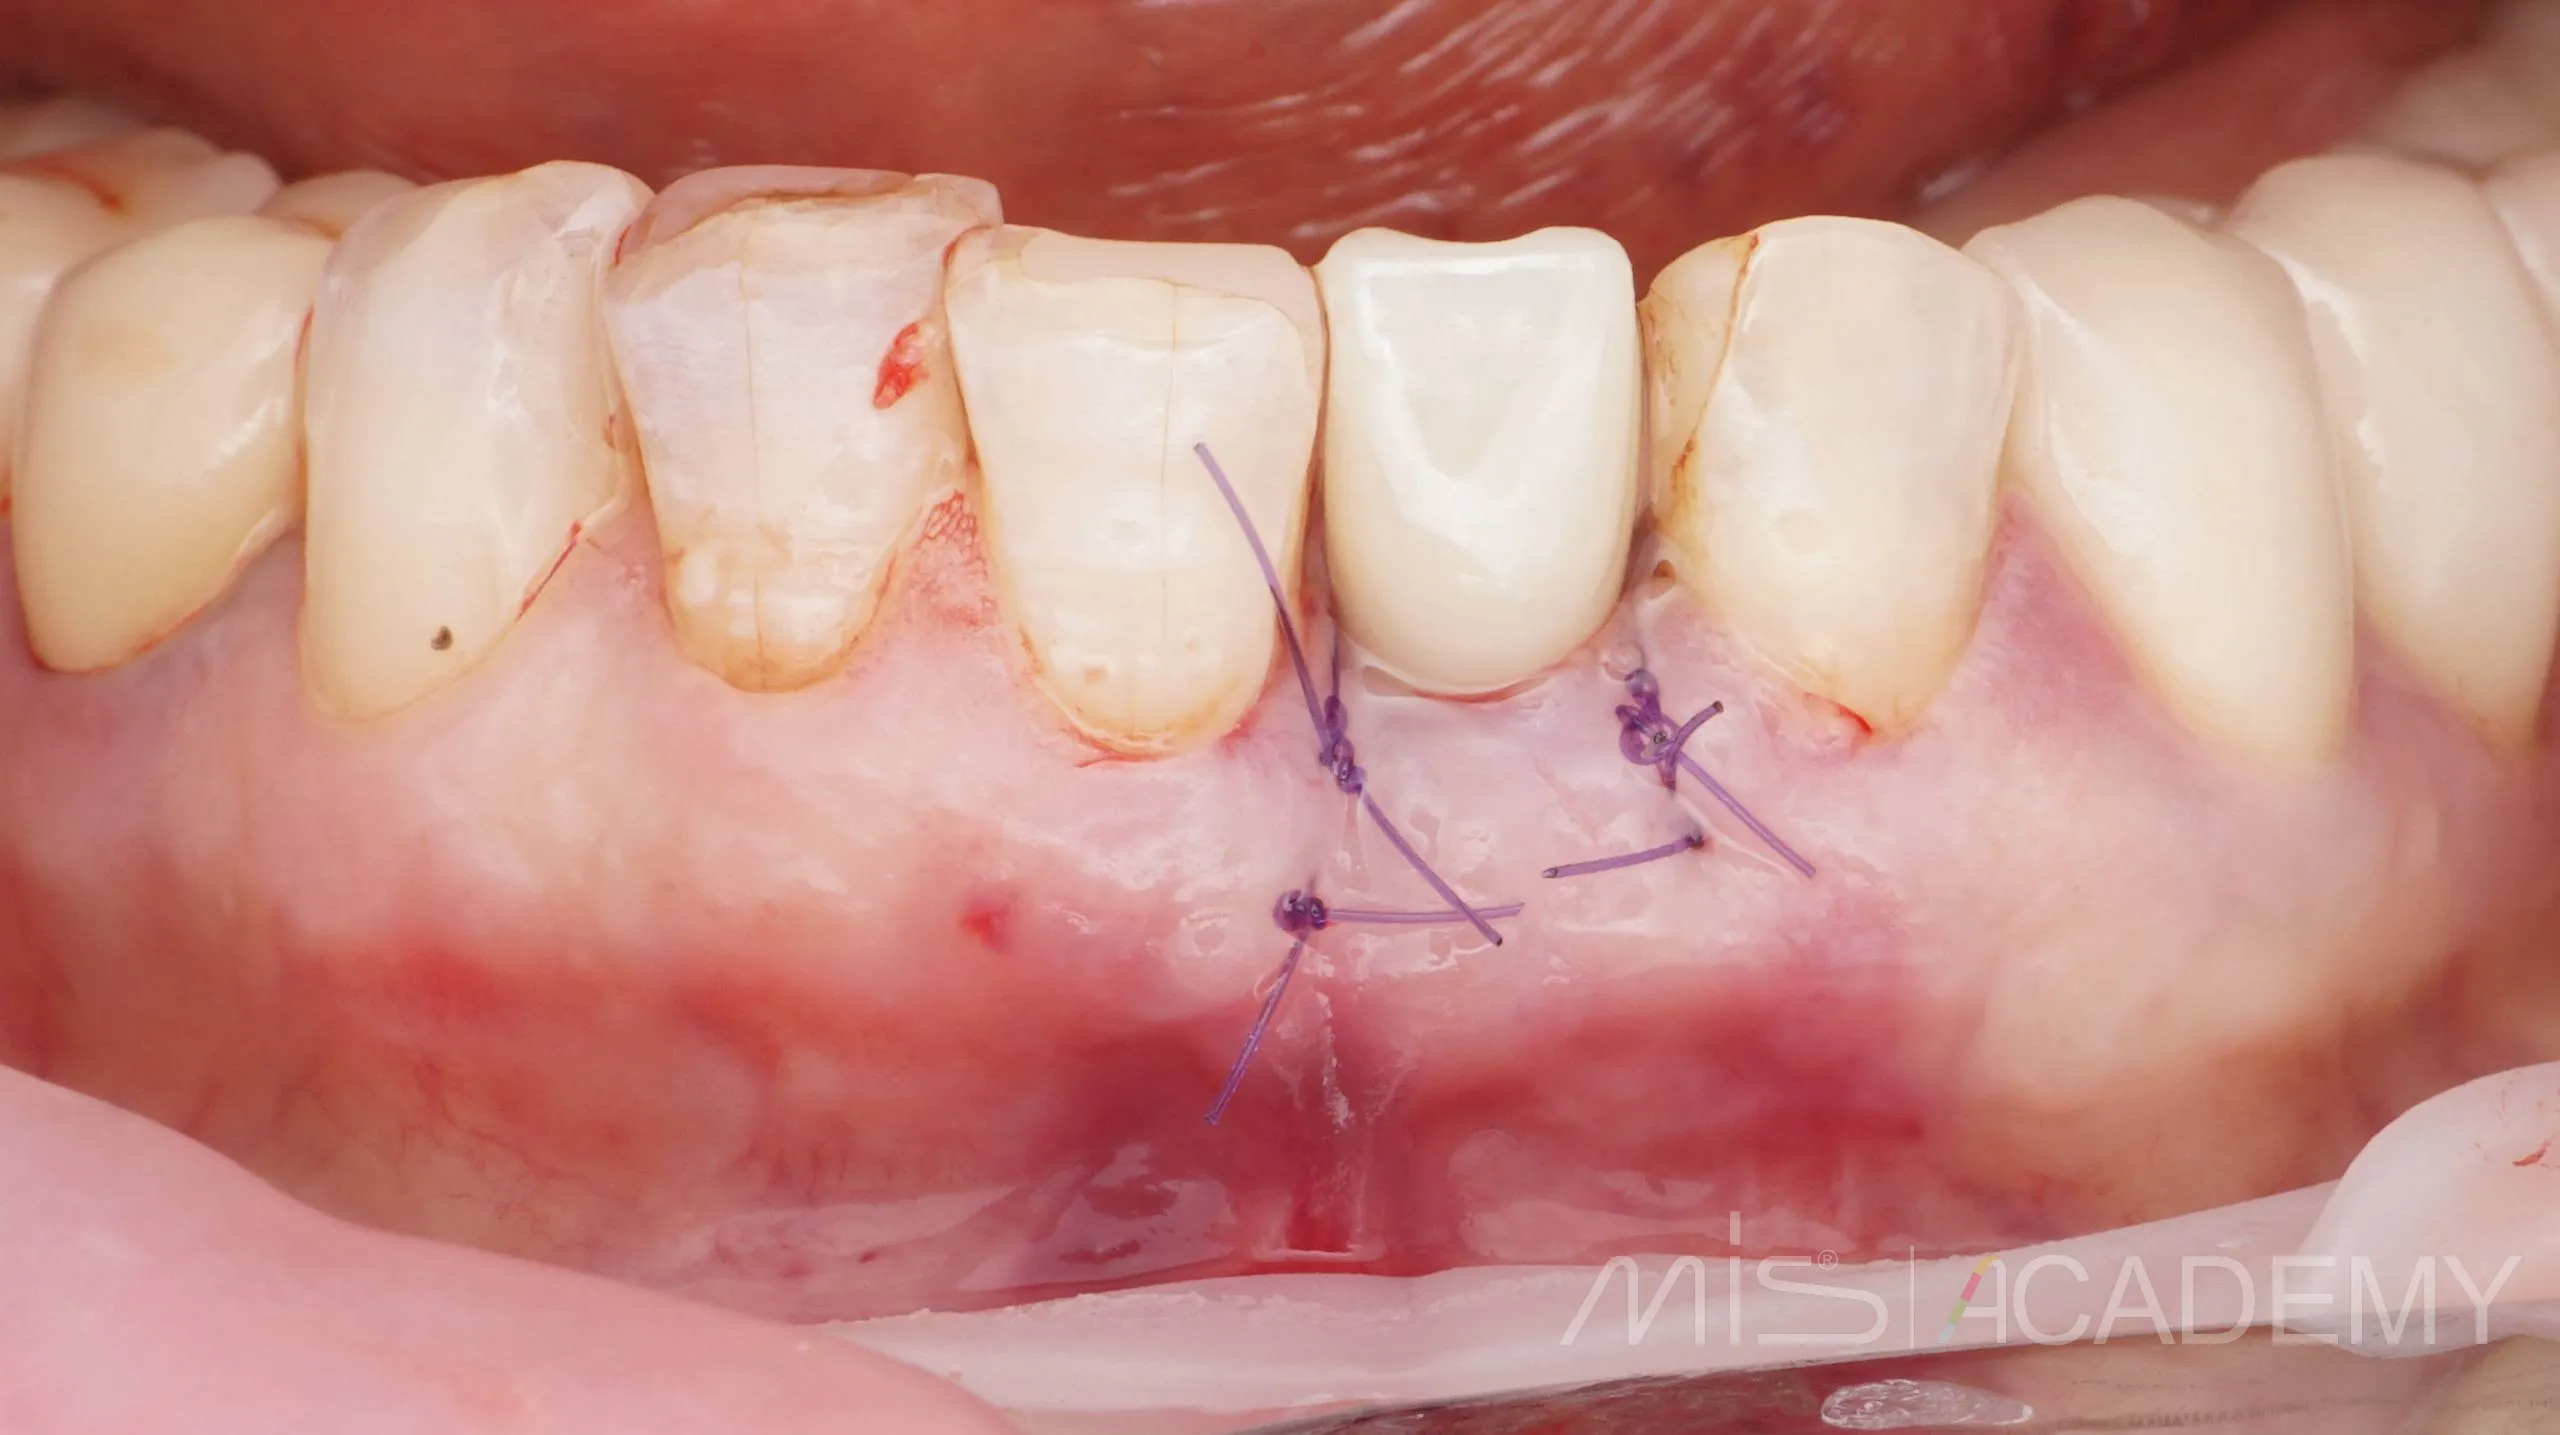

Снятие швов через 10 дней.

— Индивидуальный Zr формирователь десны на Connect абатменте